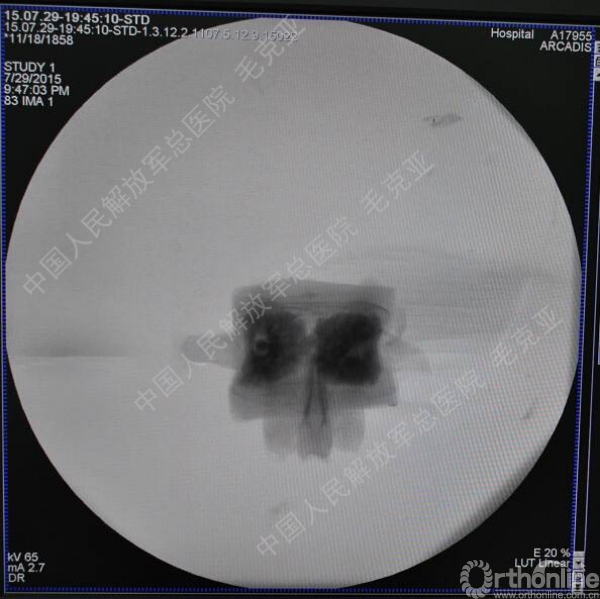

导语:随着社会老龄化的不断加速,骨质疏松性椎体压缩骨折作为一种普遍存在的老年骨科疾病已经成为现今骨科界的一个热点话题。传统的保守疗法治疗效果不佳,而现有的椎体增强技术又具有多种风险和缺陷。针对这种现状,中国人民解放军总医院毛克亚教授提供了一种新的解决方法。